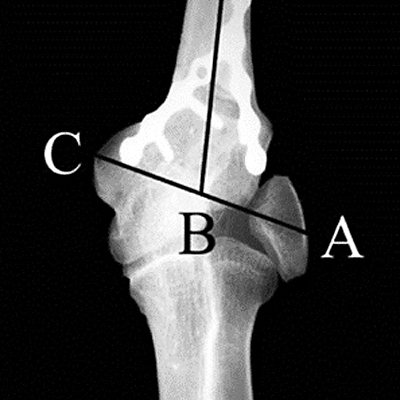

Osteotomía en cuña sustractiva supracondílea para el tratamiento del codo valgo del adulto

Gerardo Gallucci, Gonzalo Altube, Jorge Boretto, Agustín Donndorff, Ezequiel Zaidenberg, Ignacio Rellán, Pablo De Carli

316-323